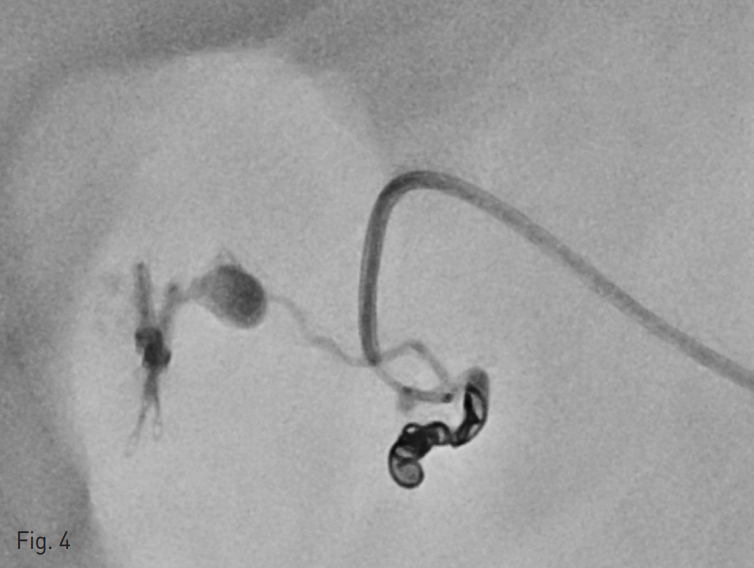

시술 중간 환자의 혈압이 떨어지기 시작하여 혈관외 유출이 있는 분지의 원위부인 위이자샘창자동맥(superior pancreaticoduodenal artery)을 microcoil 3개 (Tornado, Cook Medical, Bloomington, IN,USA)를 이용하여 막고 (Fig. 4) 근위부에서 n-butyl cyanoacrylate (NBCA; Histoacryl, B.Braun, Melsungen, Germany) + 요오드화 오일 (Lipiodol Ultra-Fluide, Guerbet, Paris, France)의 1:2.5 혼합액을 주사하여 샘창자상부동맥 (Supraduodenal artery)에 대한 색전술을 시행하였다.

Fig. 4

Three microcoils were placed at the distal branch of the superior pancreaticoduodenal artery.